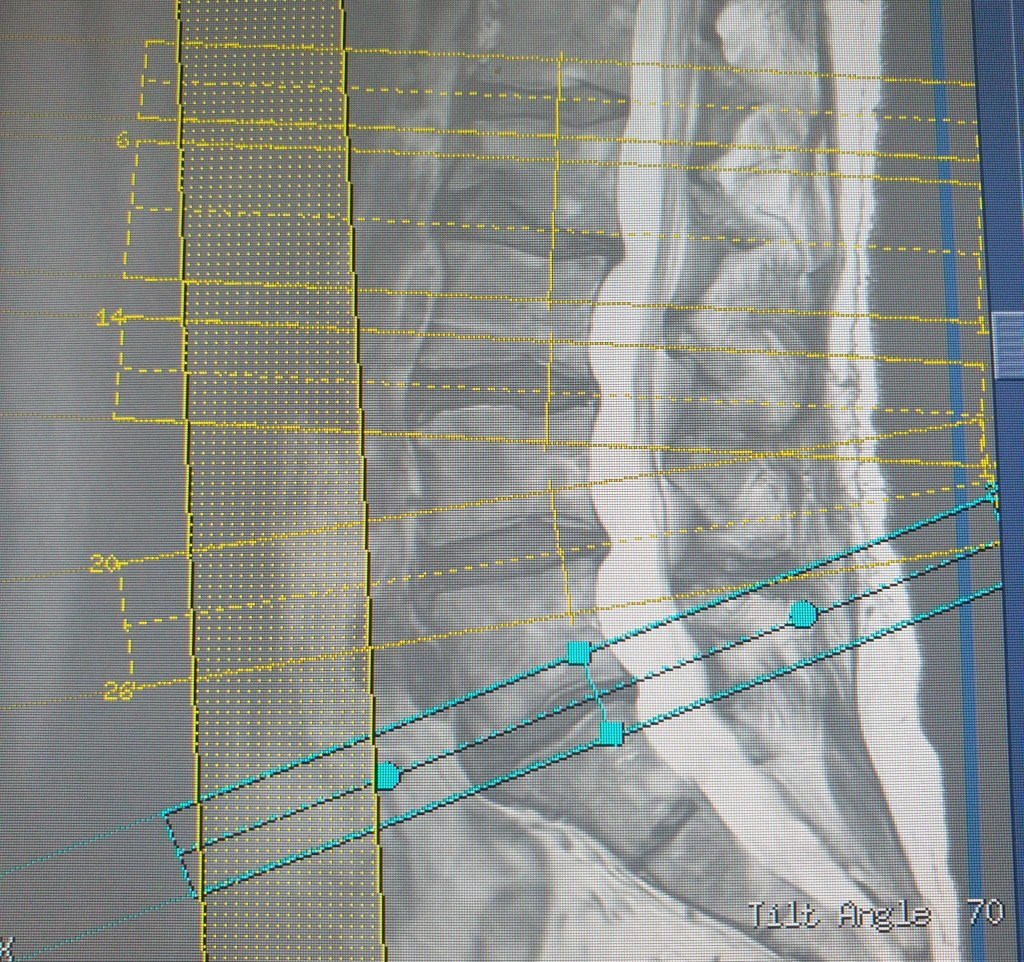

Inset lower: This is the lumbar vertebrae or, as we presumably call it in MRI, a back. Note the strong signal from the cerebrospinal fluid, which tells me that this is – yes, that’s right – a T2 weighted image. Note also the saturation band to prevent flow artifacts disturbing the field of interest, and my careful placing of volume slices through the spinal fibrocartilage, all but eliminating cross talk.